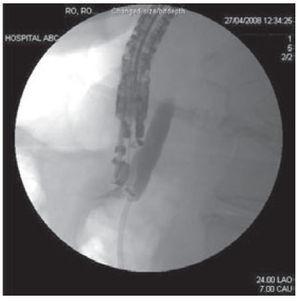

Once the wire was into the duodenal lumen several loops were formed (Figure 3) in order to avoid loosing access at the time endoscope exchange during the rendezvous procedure that was performed as previously described. (Figure 4 A-C). Using a duodenoscope (TJF-160F, Olympus) we observed that the bile duct drained from an independent and different orifice than the pancreatic duct within the ampulla. Access and drainage of the bile duct was performed sliding the duodenoscope over the guide wire; during the procedure, self-limited blood oozing occurred after biliary sphincterotomy. The patient underwent surgery next day and was discharged in good conditions.

Figure 3. Fluroscopic image showing a 0.018 inch guide wire inserted through the needle and advanced in an antegrade fashion, into the duodenum across the papillary orifice.